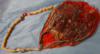

What is this image depicted of the female reproductive tract [1]

Endometriosis